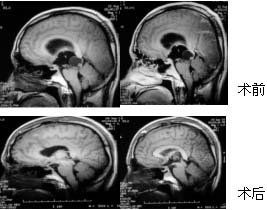

治療

對於無占位效應或無症狀的蛛網膜囊腫,無論其大小或部位均無需治療,但應定期隨診複查。手術治療多用於有症狀和囊腫有張力者,手術方式包括囊腫腹腔分流術、內鏡輔助下囊腫引流和囊壁切除術和開顱手術切除部分囊壁,使囊腫與周圍腦池溝通術。